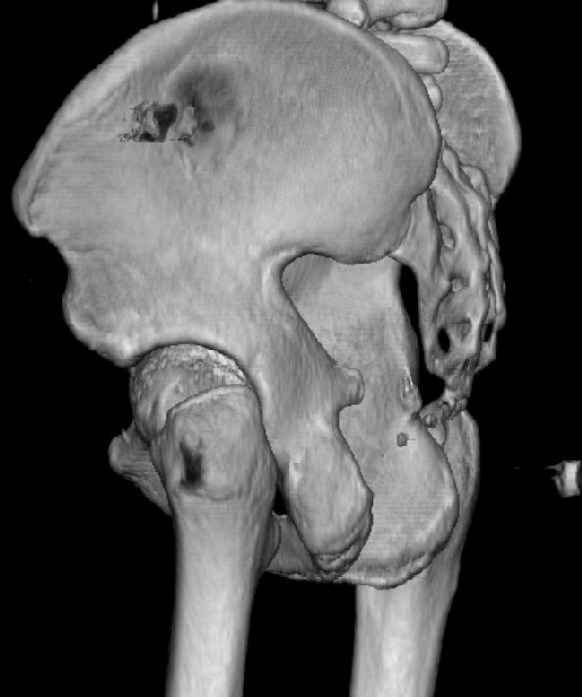

Re: Нелеченный перелом вертлужной впадины

Some more images. Does it help to guess which part of the acetabulum is displaced?